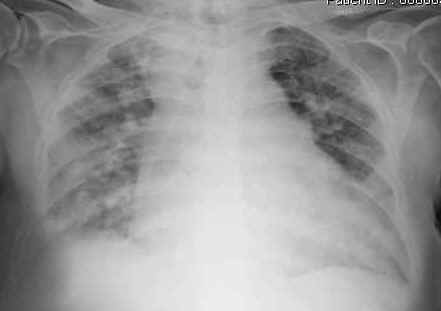

in cui non solo si indicavano le principali malattie prodotte dall’inquinamento ambientale ma anche la percentuale ingravescente di tumori ed altre malattie con l’avvicinarsi ad una causa d’inquinamento come la discarica, e lo stesso si può dire anche per gli inceneritori e le centrali a carbone.

Nel febbraio 2011 è uscito un interessante articolo sul Pais Semanal ‘Respirare pregiudica seriamente la salute’ in cui si parla proprio dei danni alla salute prodotti dalle polveri ultrafini (un milionesimo di millimetro) che attraverso i capillari degli alveoli passano nel circolo sanguigno e sono proprio le microparticelle che la Centrale TirrenoPower non controlla nelle tonnellate di polveri che escono dalle ciminiere.

Per quanto riguarda la provincia di Savona, l’Ordine dei Medici ha inviato l’anno scorso, a tutti i medici, con la sua rivista, un accurato studio scientifico in cui si evidenzia il tasso di morbilità-mortalità annuale prodotto dall’inquinamento, cui contribuisce notevolmente la Centrale TirrenoPower, superiore a quello delle altre province liguri ed uno dei più alti in Italia.